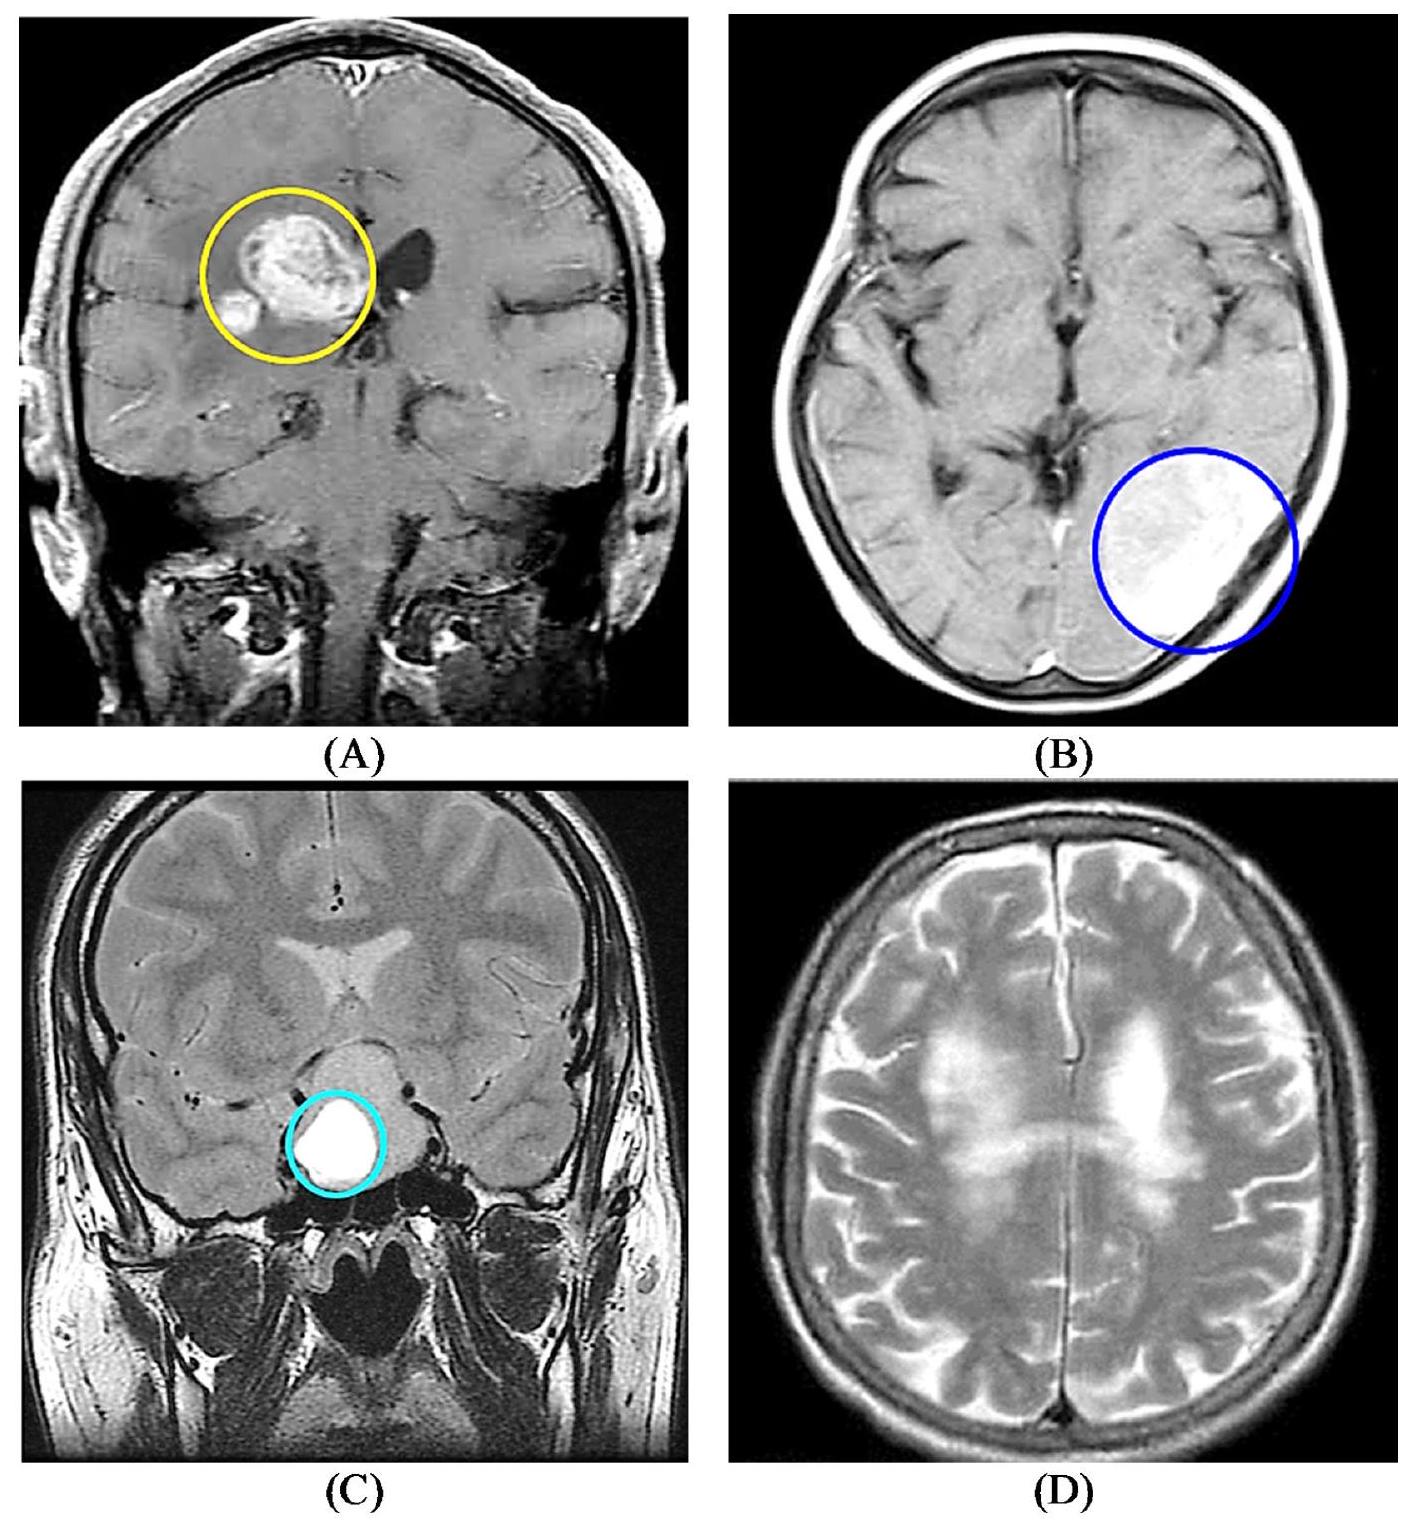

Brain tumors present a significant global health challenge, and their early detection and accurate classification are crucial for effective treatment strategies. This study presents a novel approach combining a lightweight parallel depthwise separable convolutional neural network (PDSCNN) and a hybrid ridge regression extreme learning machine (RRELM) for accurately classifying four types of brain tumors (glioma, meningioma, no tumor, and pituitary) based on MRI images. The proposed approach enhances the visibility and clarity of tumor features in MRI images by employing contrastlimited adaptive histogram equalization (CLAHE). A lightweight PDSCNN is then employed to extract relevant tumor-specific patterns while minimizing computational complexity. A hybrid RRELM model is proposed, enhancing the traditional ELM for improved classification performance. The proposed framework is compared with various state-of-the-art models in terms of classification accuracy, model parameters, and layer sizes. The proposed framework achieved remarkable average precision, recall, and accuracy values of 99.35%, 99.30%, and 99.22%, respectively, through five-fold cross-validation. The PDSCNN-RRELM outperformed the extreme learning machine model with pseudoinverse (PELM) and exhibited superior performance. The introduction of ridge regression in the ELM framework led to significant enhancements in classification performance model parameters and layer sizes compared to those of the state-of-the-art models. Additionally, the interpretability of the framework was demonstrated using Shapley Additive Explanations (SHAP), providing insights into the decisionmaking process and increasing confidence in real-world diagnosis.

- Employing CLAHE improved the visibility and clarity of important tumor features in the MRI images, thereby enhancing the subsequent analysis and classification tasks.

Brain tumor dataset